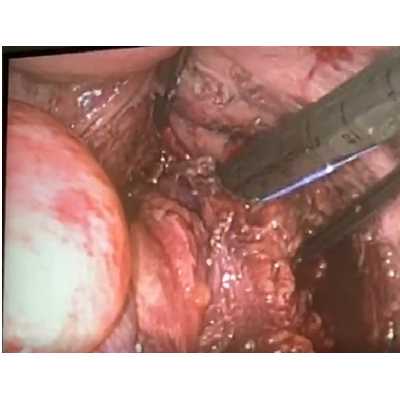

LAPAROSCOPIC SURGERY FOR PANCREATIC TUMOUR

LAPAROSCOPIC WHIPPLES PROCEDURE